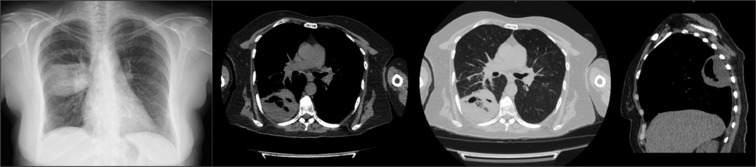

胸部超声(TUS)是一种长期建立的成像方式,在诊断许多胸膜实质疾病方面具有公认的有效性和可靠性。肺脓肿(LA)是一种以肺实质内液化性坏死和空化为特征的传染病,多见于免疫抑制患者或有多种危险因素的患者。它的治疗包括有效的抗生素治疗,在极少数情况下,引流或手术。在可行的情况下,从LA获取样本对于根据培养物中鉴定的病原体启动靶向治疗至关重要。在这个病例报告中,我们提出了一个44岁的女性患者住院的洛杉矶。脓肿通过超声显像,在超声引导下取样,并在持续的超声监测下成功处理。

Thoracic ultrasonography (TUS) is a long-established imaging modality with proven efficacy and reliability in the diagnosis of numerous pleuro-parenchymal diseases. Lung abscess (LA) is an infectious disease characterized by liquefactive necrosis and cavitation within the pulmonary parenchyma, typically occurring in immunosuppressed patients or those with various risk factors. Its treatment involves effective antibiotic therapy and, in rare cases, drainage or surgery. Obtaining a sample from the LA, when feasible, is crucial for initiating targeted therapy based on the pathogen identified in the culture. In this case report, we present a 44-year-old female patient hospitalized for an LA. The abscess was visualized via TUS, sampled under ultrasound guidance and successfully managed with ongoing ultrasonographic monitoring.